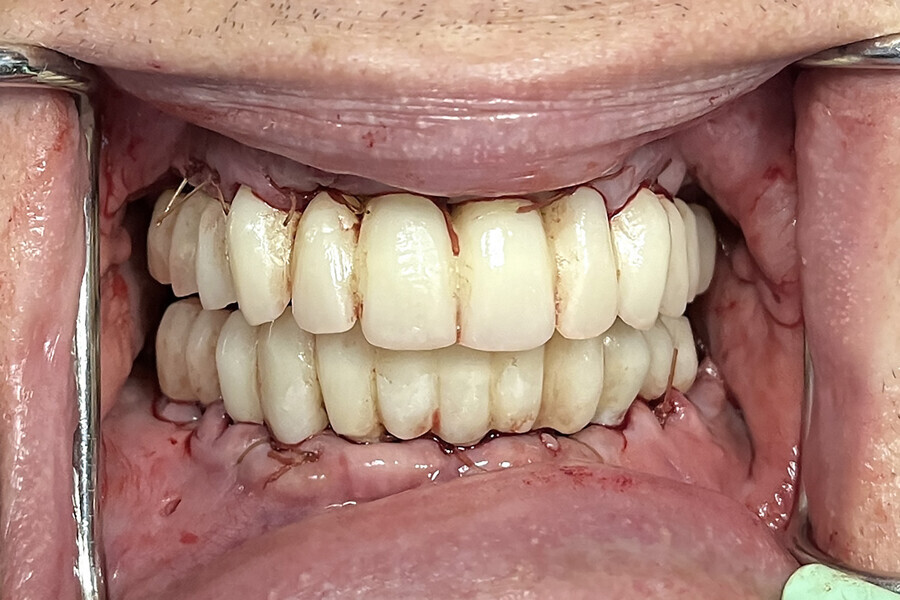

Fig. 16b: Retracted intra-oral view.

Fig. 17b: Retracted intra-oral view.

The data collected was sent through a scanning software portal (Medit Scan for Clinics) to the dental laboratory with requested changes for correction of the desired smile design. Utilising advanced planning features in the design software (exocad), the midline and tooth size changes were corrected. 3D-printed maxillary and mandibular PMMA restorations were used for try-in using the direct-to-MUA screws (Vortex LA VIS; Fig. 16a). Fit, phonetics, aesthetics and occlusion were evaluated and confirmed using digital articulation (OccluSense; Fig. 16b). The patient was extremely satisfied with the printed try-ins. Since no adjustments were required, the patient was allowed to leave with the printed try-ins as new provisional restorations made from extra-strong resin. The new provisional restorations were worn for ten days to confirm form and function. The final shade was chosen, and metal-free monolithic zirconia restorations were then fabricated by the laboratory.